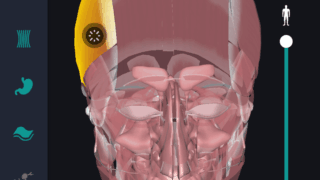

はじめに 本記事では、人体解剖学における専門的な部位の知識を始めに、効果的な勉強法についてご説明します。 人体解剖学では様々な器官や筋肉、骨の名称を覚えるだけではなく、体のどの位置に存在するのかまで覚えなければなりません。そのため、できるだ...